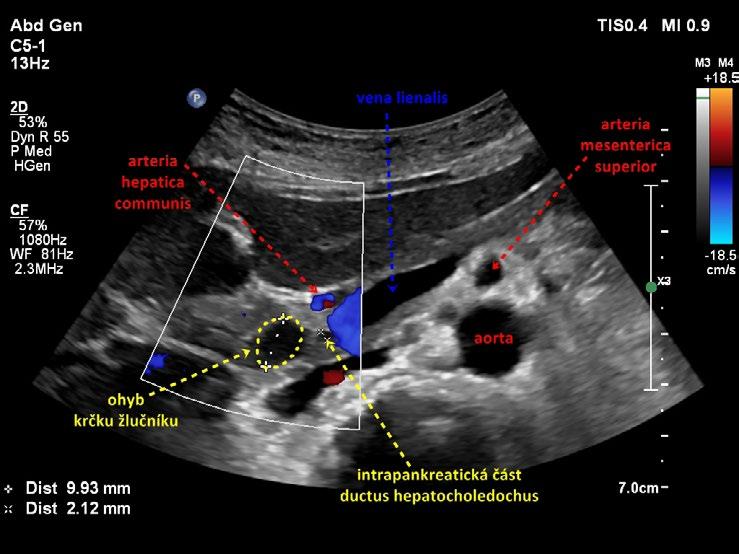

Kromě běžného kapkovitého tvaru mívá žlučník řadu tvarových variací. Časté je zahnutí žlučníku v oblasti krčku (obr. 1.4), těla (obr. 1.5) nebo fundu. Zahnutí bývá mnohdy i několikanásobné (obr. 1.6) a může v některých rovinách zobrazení vytvářet falešný dojem septace (obr. 1.7). Skutečné septum žlučníku je ale vzácné (0,02 % pitevních nálezů). Nalézá se například při duplikatuře žlučníku, při které je lumen rozděleno podélným septem a každá z polovin žlučníku je drénována vlastním ductus cysticus. Ohyb v infundibulu a krčku může imitovat dilataci hepatocholedochu (obr. 1.8). Při nízce odstupujícím ductus cysticus se ohyb krčku žlučníku může sumovat s hlavou pankreatu a vytvářet mylný dojem dilatace intrapankreatické části hepatocholedochu. Pečlivé vyšetření hlavy pankreatu a celého průběhu hepatocholedochu ve vícero zobrazovacích rovinách vede k odlišení ohybu žlučníku od vlastního nedilatovaného intrapankreatického hepatocholedochu (obr. 1.9).

Obr. 1.9 Nízce odstupující ductus cysticus: odlišení ohybu krčku žlučníku od intrapankreatické části ductus hepatocholedochus